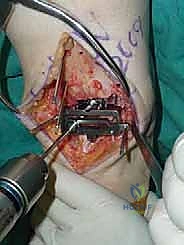

4. وضع أدلة القطع (Jig Placement and Alignment)

تعتمد دقة الجراحة على المحاذاة الصحيحة. يتم استخدام أجهزة توجيه متطورة (Jigs) تثبت على عظمة الساق باستخدام دبابيس معدنية. يتم التحقق من صحة الزوايا والمحاور باستخدام جهاز الأشعة السينية المباشر داخل غرفة العمليات (C-arm Fluoroscopy). يضمن الدكتور هطيف أن يكون القطع موازياً للأرض تماماً عند وقوف المريض.

5. القطع العظمي الظنبوبي (Tibial Bone Cut)

باستخدام منشار جراحي دقيق التذبذب، يتم إزالة شريحة رقيقة جداً (بضعة مليمترات) من السطح السفلي التالف لعظمة الظنبوب. يتم القطع بحذر شديد لتجنب إصابة الأوتار الخلفية أو الأوعية الدموية.

6. القطع العظمي الكاحلي (Talar Bone Cut)